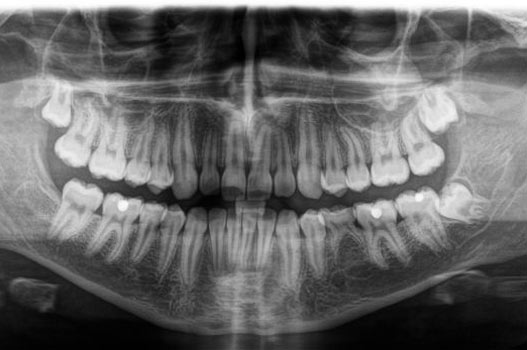

Panoramaschichtaufnahme

Auf der Panoramaschichtaufnahme beurteilt der Kieferorthopäde die Zähne und ihre Wurzeln, die Kiefergelenke, die Nasennebenhöhlen, die allgemeine Knochendichte und die Zahnstellung im Kiefer.

Bei Kindern und Jugendlichen überprüft der Fachzahnarzt, ob alle bleibenden Zähne, einschließlich der Weisheitszähne, angelegt sind und wie viel Platz für den Zahndurchbruch vorhanden ist. Dies hilft dem Kieferorthopäden, den optimalen Zeitpunkt für den Beginn einer kieferorthopädischen Behandlung zu bestimmen.

Das Übersichts-Röntgenbild gibt auch Hinweise auf mögliche Behandlungsschwierigkeiten, wie fehlende oder verlagerte Zähne. Insbesondere bei Folgebehandlungen ist es wichtig, Anzeichen für Wurzelresorptionen frühzeitig zu erkennen. Auch Füllungen, Kronen, Brücken, Implantate oder Karies können analysiert werden.